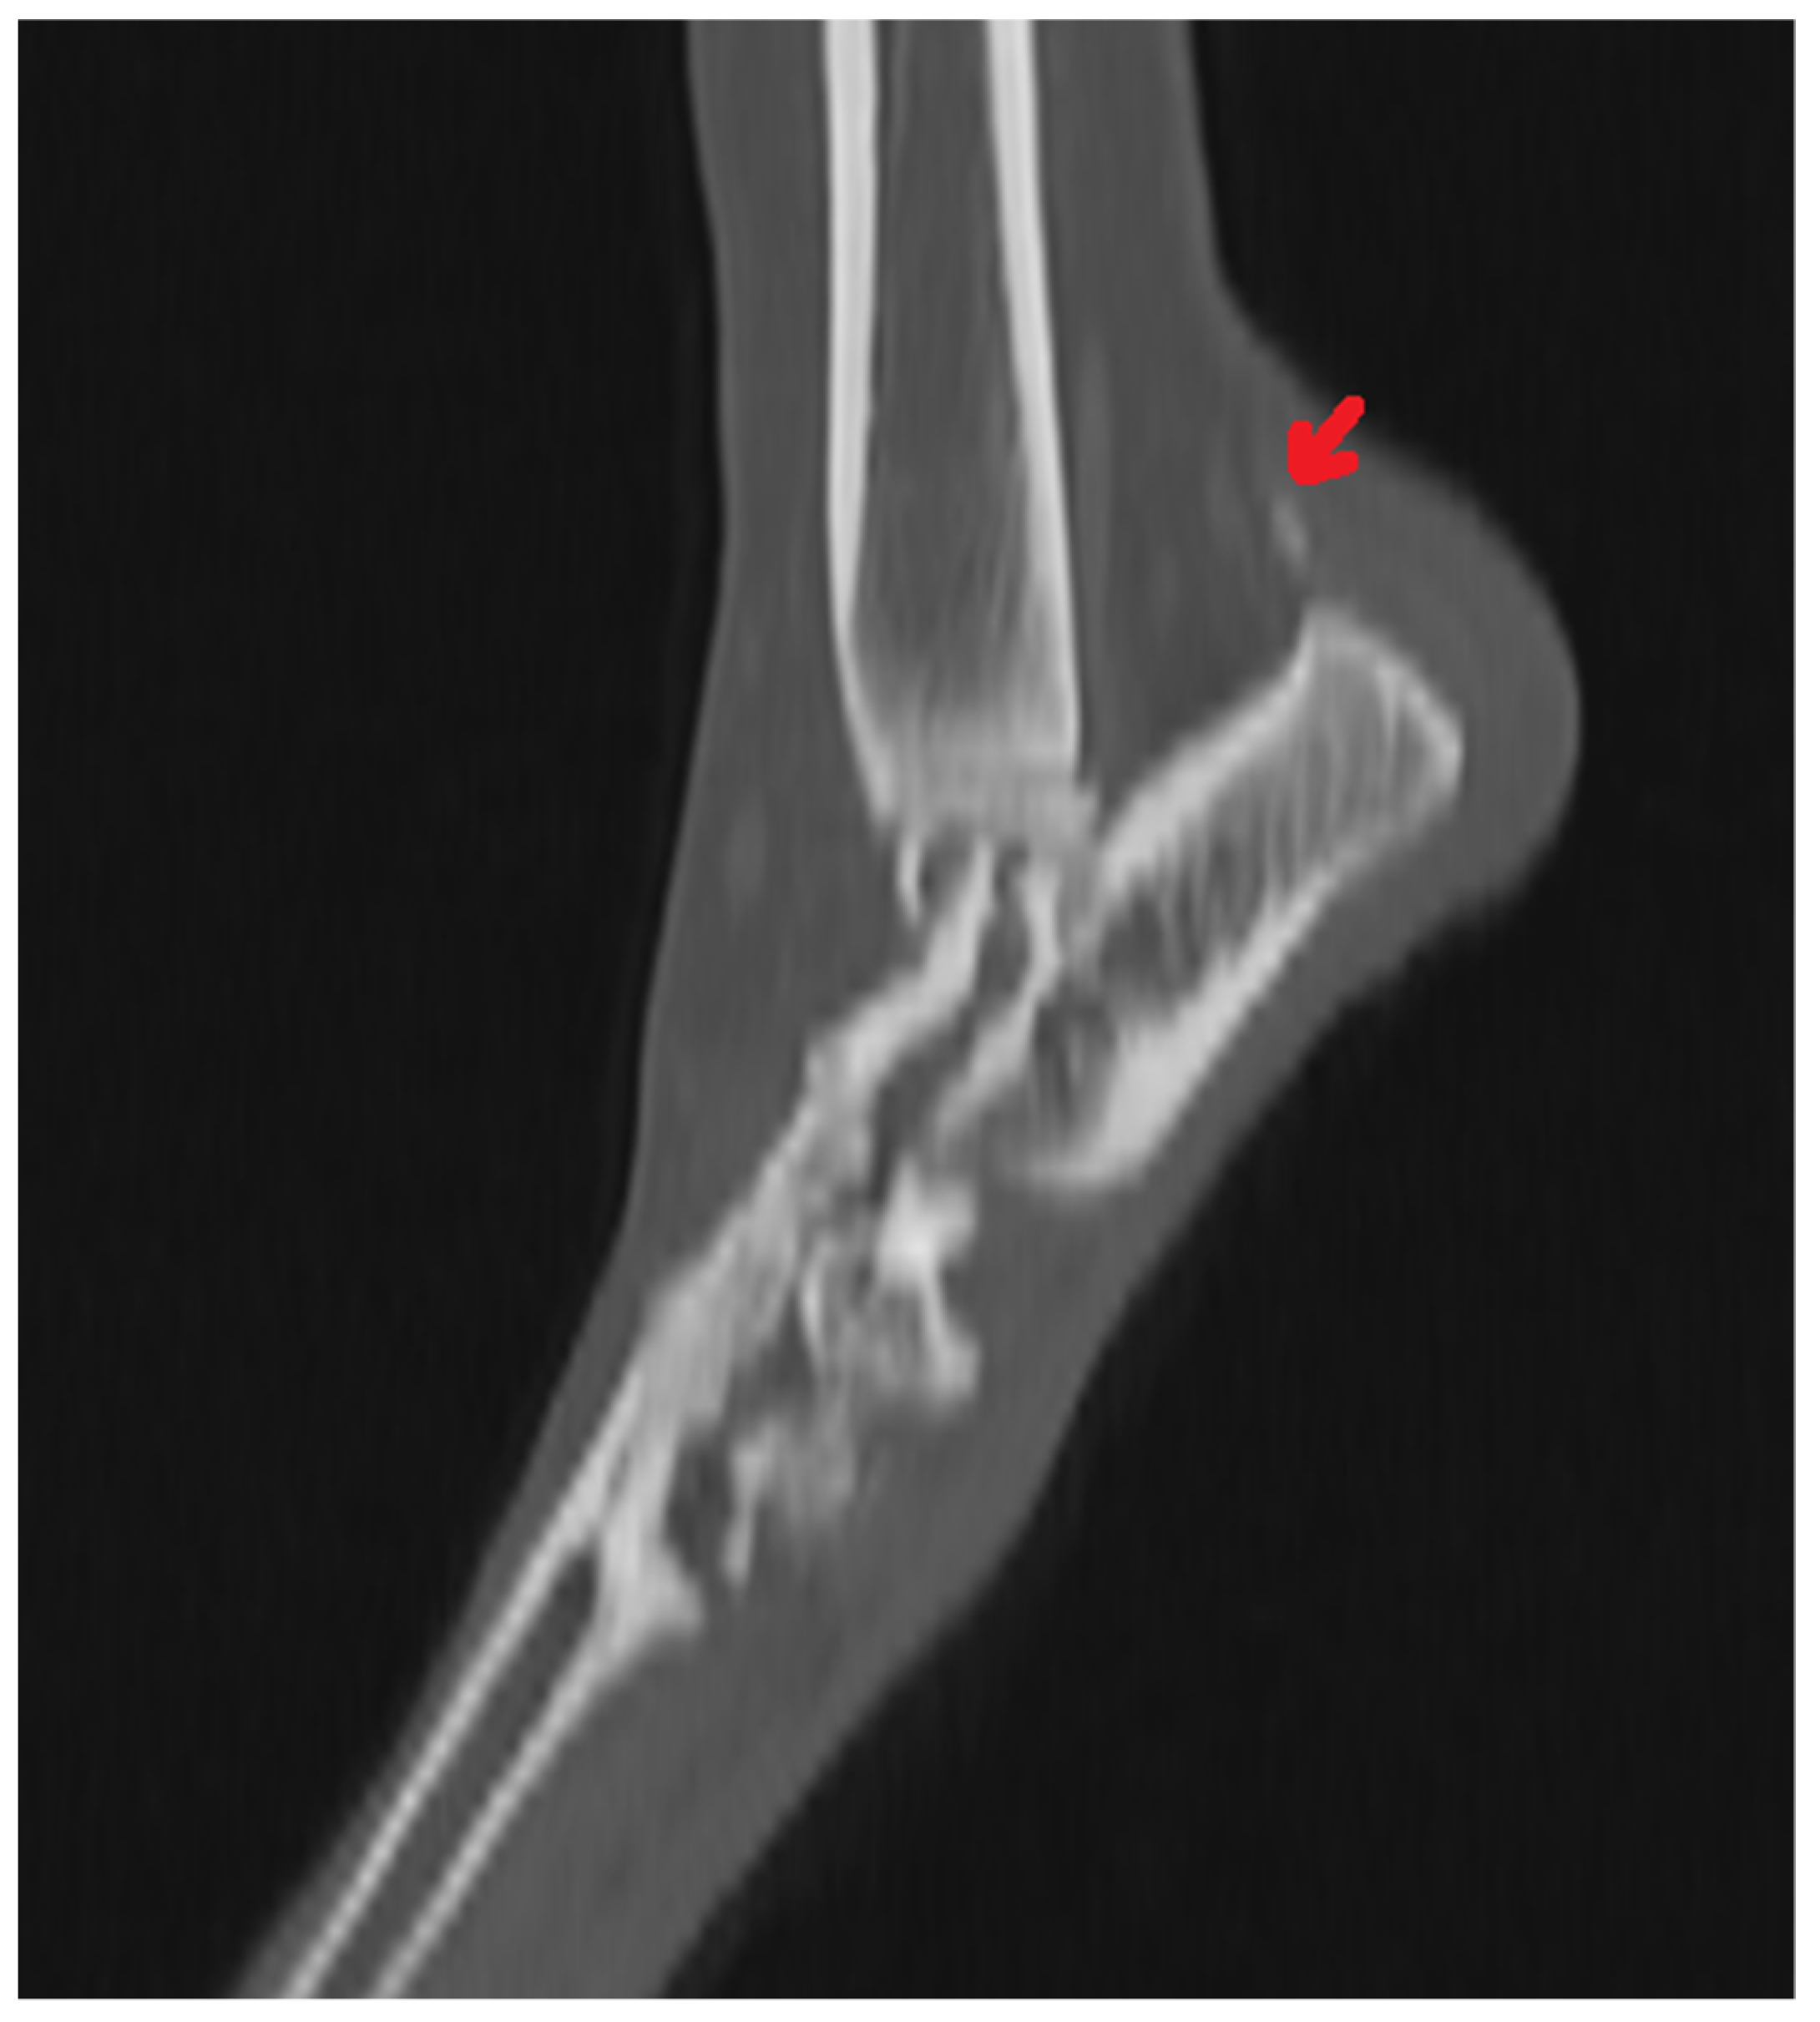

4. Fractures of the Tarsal Bones